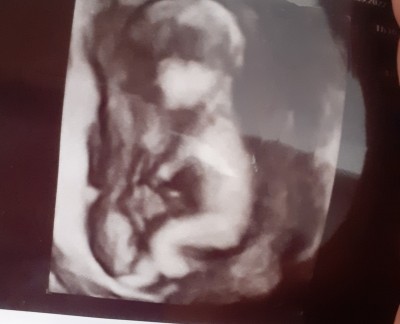

16 haftalik 8 haftalik 18 haftalik ultrasonlar tahmin lutfen

Kız şimdiye kadar öğrenmen gerekirdi ogrenmedin ki daha 18 haftalık olmuş,ben 12 de ogrenmistim

Maalesef kordon dolayısı ile ayrintiliya kaldık sizce tahmininiz neye benziyo haftaya salı ayrıntılı da gorcez inşallah

Benim içimden kız geçti canım sağlıkla gelsin